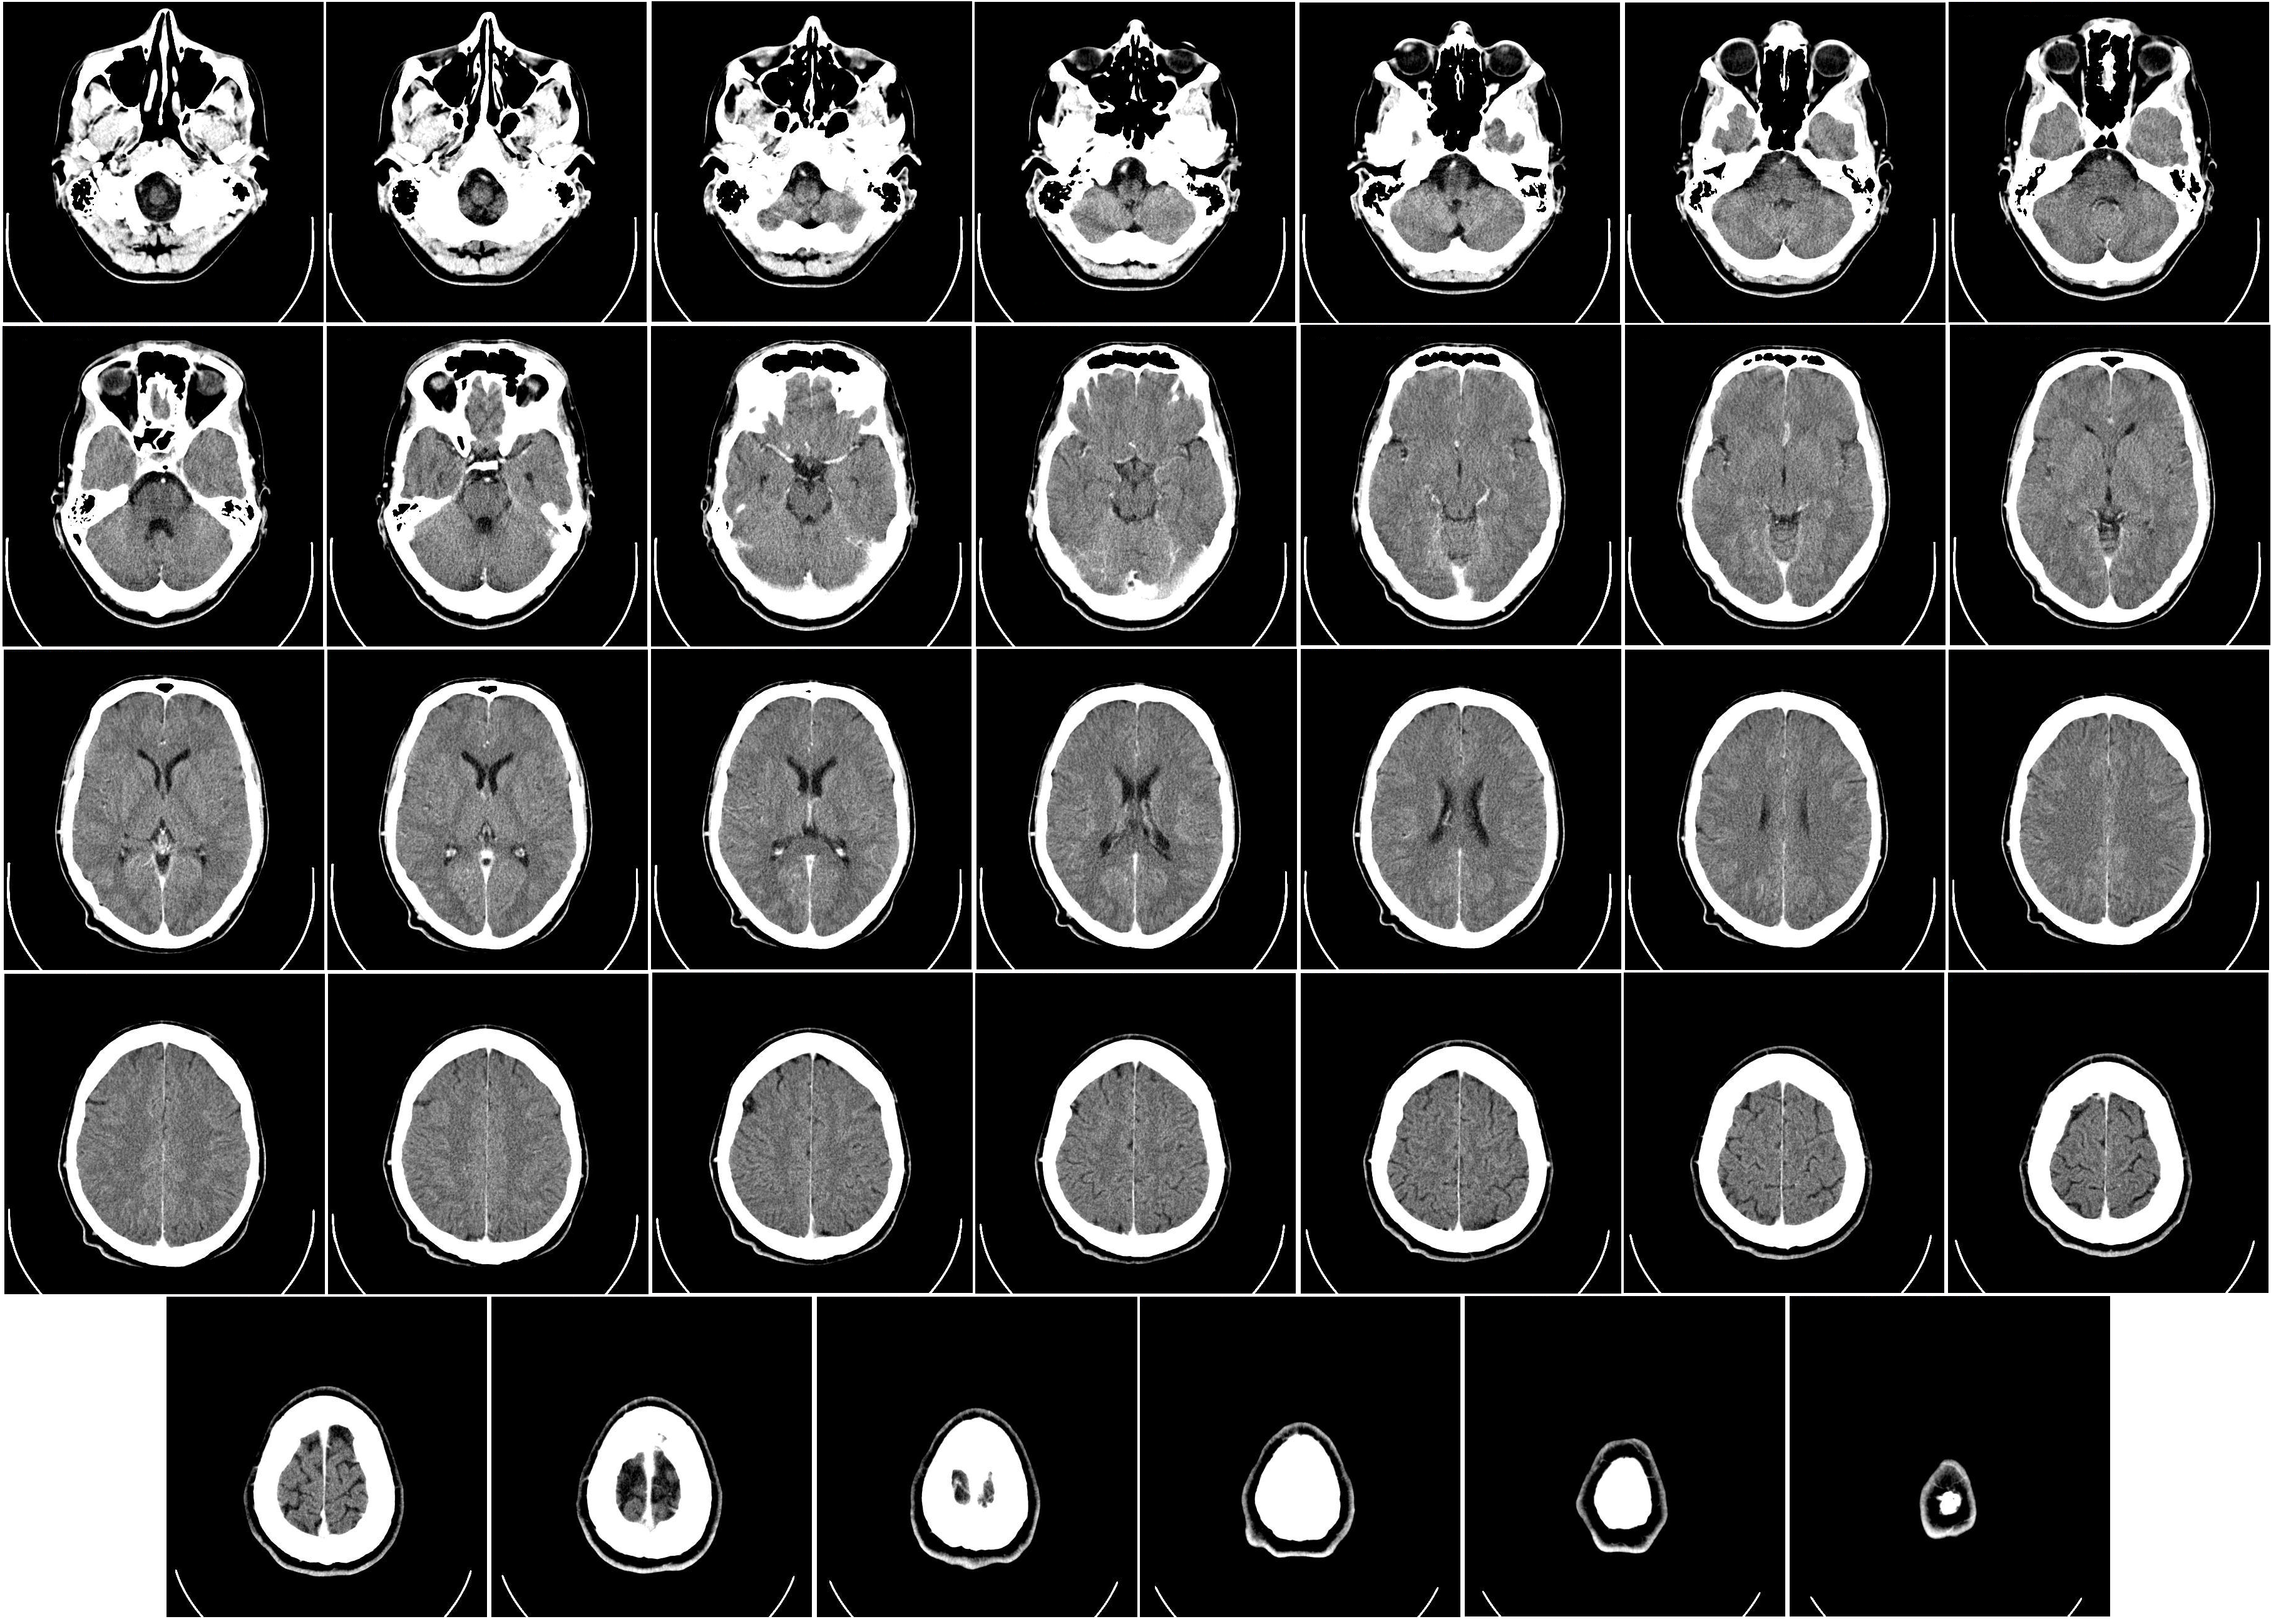

國際貴金屬價格近期大漲,近日有民眾用Sim卡提煉黃金,又出現有人用含銀的醫療電腦斷層掃描(CT)廢膠片,提煉白銀,但相關人士提醒私自提煉白銀不僅污染環境,更可能觸犯刑法。

《極目新聞》報道,一名在西北地區從事CT廢膠片回收的業者表示,隨着白銀價格上漲,自去年12月起,含銀醫療CT廢膠片的回收量明顯增加:「以前主要是從廢品收購站收,最近透過社交平台來詢問的人明顯變多。」他指出,CT廢膠片之所以能「變廢為寶」,關鍵在於部分膠片含有可回收的銀元素,但並非所有CT膠片都含銀。

該業界人士透露:「銀價暴漲前,CT片每斤(約500公克,12張)約10元人民幣(約11.2港元),現在每斤35元(約39.3港元)左右。」他強調僅從事回收,不涉及提煉白銀:「提煉白銀需要相關手續,私自提煉涉嫌違法。」

不過,根據司法資料顯示,一對夫妻收購印刷廠廢底板及醫院CT廢膠片,自行提煉白銀13.5公斤,非法獲利6萬元(約6.74萬港元)。而他們因污染環境罪被判處緩刑,並合計罰款7萬元(約7.86萬港元),得不償失。